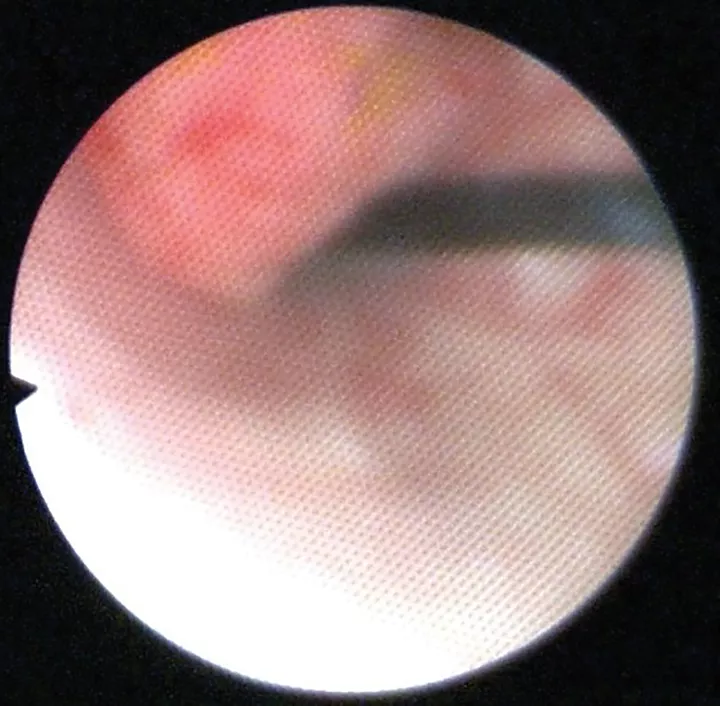

Polypoid Cystitis Causing Recurrent Hematuria in a Dog Clinician's Brief Epistaxis Dog Clinician's Brief So, you are at home with your pet and a bloody nose starts and does not seem to be stopping. Epistaxis in dogs can be extremely unsettling for the pet owner. The dog is an indoor pet that only goes outside. In 56 dogs, epistaxis was found to be secondary to a systemic disease: The face should be examined for. Epistaxis Dog Clinician's Brief.